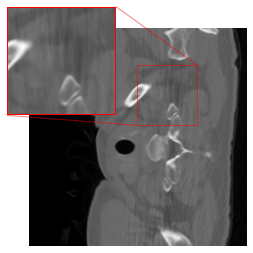

Figure 4 provides visual insights into the reconstruction process. It showcases results for three test samples from the LoDoPaB-CT test dataset. The first column displays the ground truth, while the second column showcases the outcome of the low-dose FBP, serving as the initial stage in our method. The subsequent stage enhances the FBP result using a DRUNet, which is depicted in the third and fourth columns. The third column illustrates the enhanced result when the DRUNet architecture is trained from scratch, while the fourth column portrays the enhanced result obtained with fine-tuning the pretrained DRUNet. It is evident from the visualizations that the proposed two-stage method consistently enhances basic FBP results. Moreover, working with fine-tuning yields slightly better metrics, as evidenced by improvements in PSNR and SSIM. These observations are in line with the quantitative findings presented in Table V.